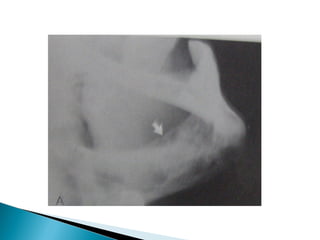

 Kidney:Calcinosis,stone formation,recurrent

•   Renal calculi,Nephrocalcinosis